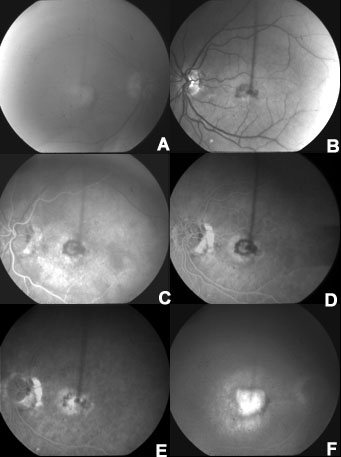

Figure 3. Clinical phenotype of AMD patient with hemicentin Gln5345Arg mutation

Red free image of right eye with a disciform scar and significant lens opacities (A) and left eye with a subfoveal choroidal neovascular membrane (B). Fluorescein angiogram of left eye at 25 s with early filling of a subfoveal choroidal neovascular membrane (C), 57 s (D), and 3 min (E). Late stage fluorescein of the right eye with a disciform scar (F).